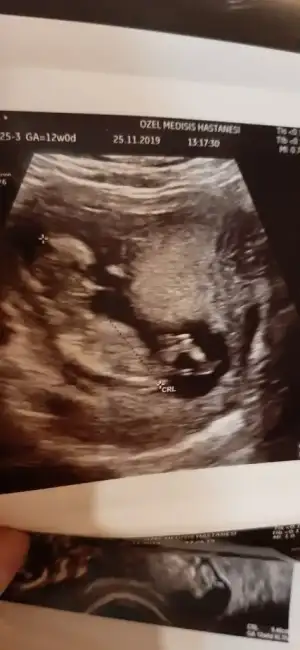

ERKEKMİ CANM... NUB İÇİN BU AÇIDAN BAKILMIYO CANISIKizlar nub teorisi bu açidan da ise yariyor mu bilen varsa yorum yaparsa sevinirim insan meraklaniyor işte❣

Yok canim doktor kesin biseysoyleyemiyorum dediERKEKMİ CANM... NUB İÇİN BU AÇIDAN BAKILMIYO CANISI

TESTİSLER KIZLARDAKİ DUDAKLARA DA BENZİYO OLABİLİR OYUZDEN NET DEMEMİŞTİR...YANDAN ÇEKİLMİŞ USG YOKMU YATARKEN FALANYok canim doktor kesin biseysoyleyemiyorum dedi

var canim ama burda hic belli degilTESTİSLER KIZLARDAKİ DUDAKLARA DA BENZİYO OLABİLİR OYUZDEN NET DEMEMİŞTİR...YANDAN ÇEKİLMİŞ USG YOKMU YATARKEN FALAN

BEN ERKEK DİYORUM =)var canim ama burda hic belli degil

ögrenince paylasiyim sizinle![]()

MERAKLA BEKLİYORUM NE ZAMAN BİDAKİ KONTROL

10 gun sonra tekrar bakabiliriz dedi bizim 10 gun sonra gidince dogum paketindeki kontrollerimizden dusmedigi icin.oyle dediMERAKLA BEKLİYORUM NE ZAMAN BİDAKİ KONTROL